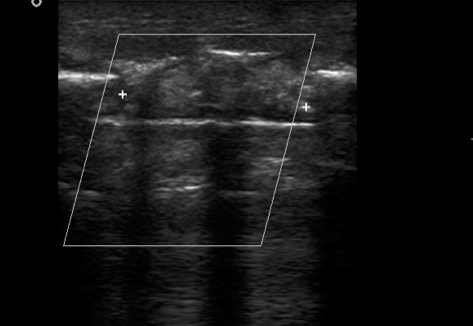

Cortical breach with intervening gap fills up with hypoechoic granulation tissue, evolving into bony matrix. This process is sonographically accessible to evaluation with greater accuracy and sensitivity in predicting optimal vs sub-optimal healing . Early intervention at 4-6 weeks post fracture can help reduce morbidity dramatically

GRANULATION STAGE: soft hypoechoic callus + >5 vs + R.I. 0.50-0.70---2 wk

FIBROUS STAGE: Organized callus echo T.A.Ms. + vs ….3 wks

First screen USG at 4 weeks

CARTILAGENOUS STAGE: Long. oriented parallel to the fracture ends with speckled dots of mineralization+ vascularity…4 wk

OSSEOUS STAGE : Echogenic callus with acoustic shadowing and obscured medullary cavity / IM nail …5-6 wks